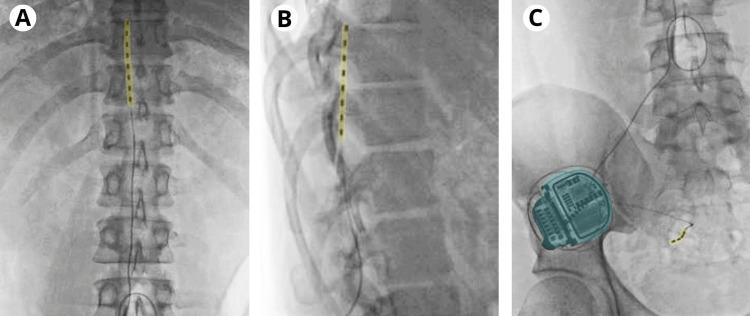

Painful postsurgical neuropathy is an adverse event inherent to a wide variety of surgical treatments, so its diagnosis and specialized treatment are essential to maintaining the quality of life of the people who suffer from it. We present the case of a 31-year-old male with neuropathy of the genitofemoral nerve diagnosed by electromyography, resulting in intractable left testicular and thigh pain associated with a recent history of ipsilateral inguinal hernioplasty. After assessment by pain medicine and motor and sensory tests, a neurostimulator was placed in T8-T9 with action at the L1-L2 level, as well as a simultaneous electrode in S3, generating optimal pain relief and recovery of functionality.

术后疼痛性神经病变是多种外科治疗中固有的不良事件,因此其诊断和专科治疗对于维持患者的生活质量至关重要。我们报告一例31岁男性,经肌电图诊断为生殖股神经病变,导致顽固性左侧睾丸和大腿疼痛,近期有同侧腹股沟疝修补术病史。在经过疼痛医学评估以及运动和感觉测试后,在T8 - T9置入神经刺激器,作用于L1 - L2水平,同时在S3置入电极,实现了最佳的疼痛缓解和功能恢复。